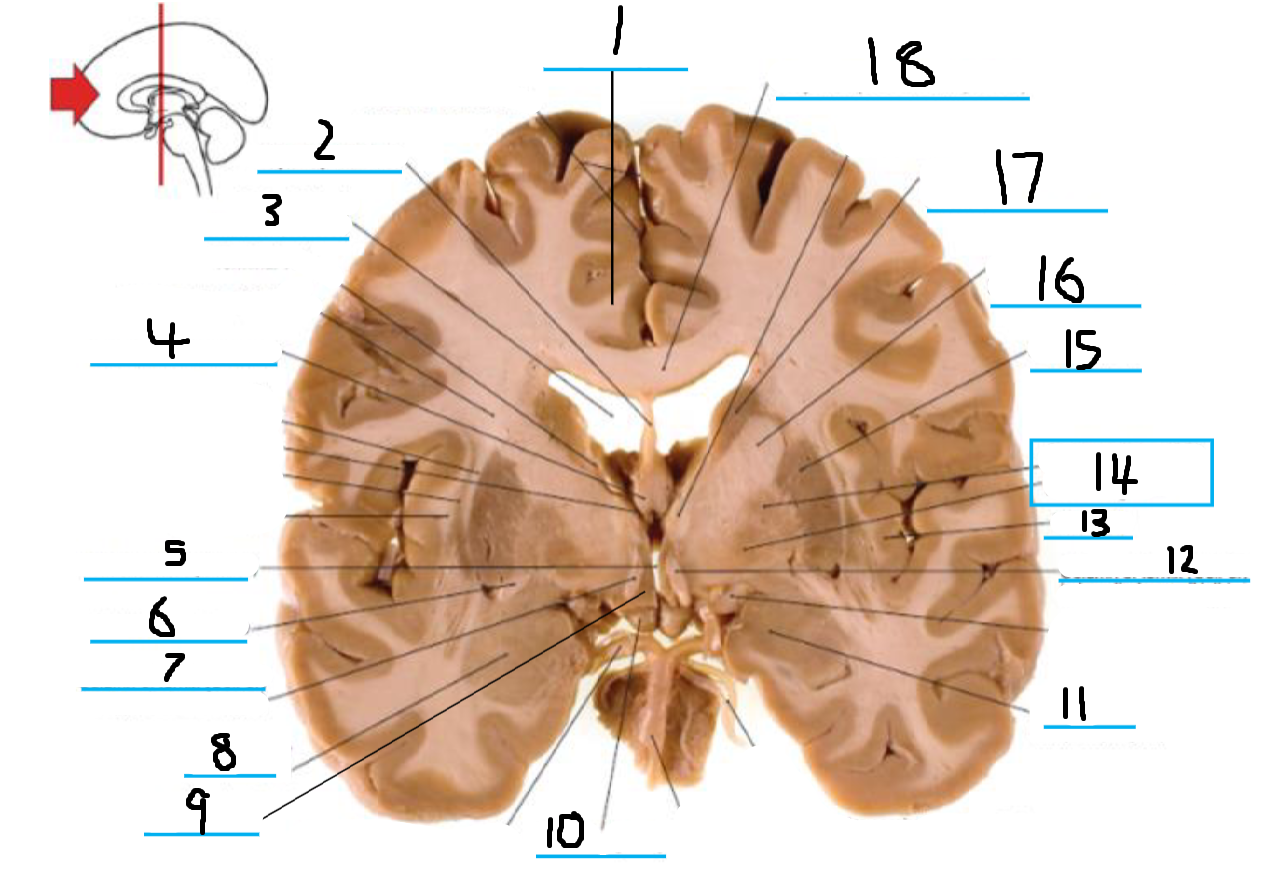

#1 is the:

Cingulate Gyrus

#2 is the:

Septum Pellucidum

#3 is the:

Lateral Ventricle

#4, #7, and #12 is the:

Fornix

#5 is the:

Third Ventricle

#6 is the:

Anterior Commissure

#8 and #11 is the:

Amygdala

#9 is the:

Hypothalamus

#10 is the:

Mammillary Body

#13 is the:

Insula

#14 is the:

Globus Pallidus

#15 is the:

Putamen

#16 is the:

Internal Capsule

#17 is the:

Caudate

#18 is the:

Corpus Callosum